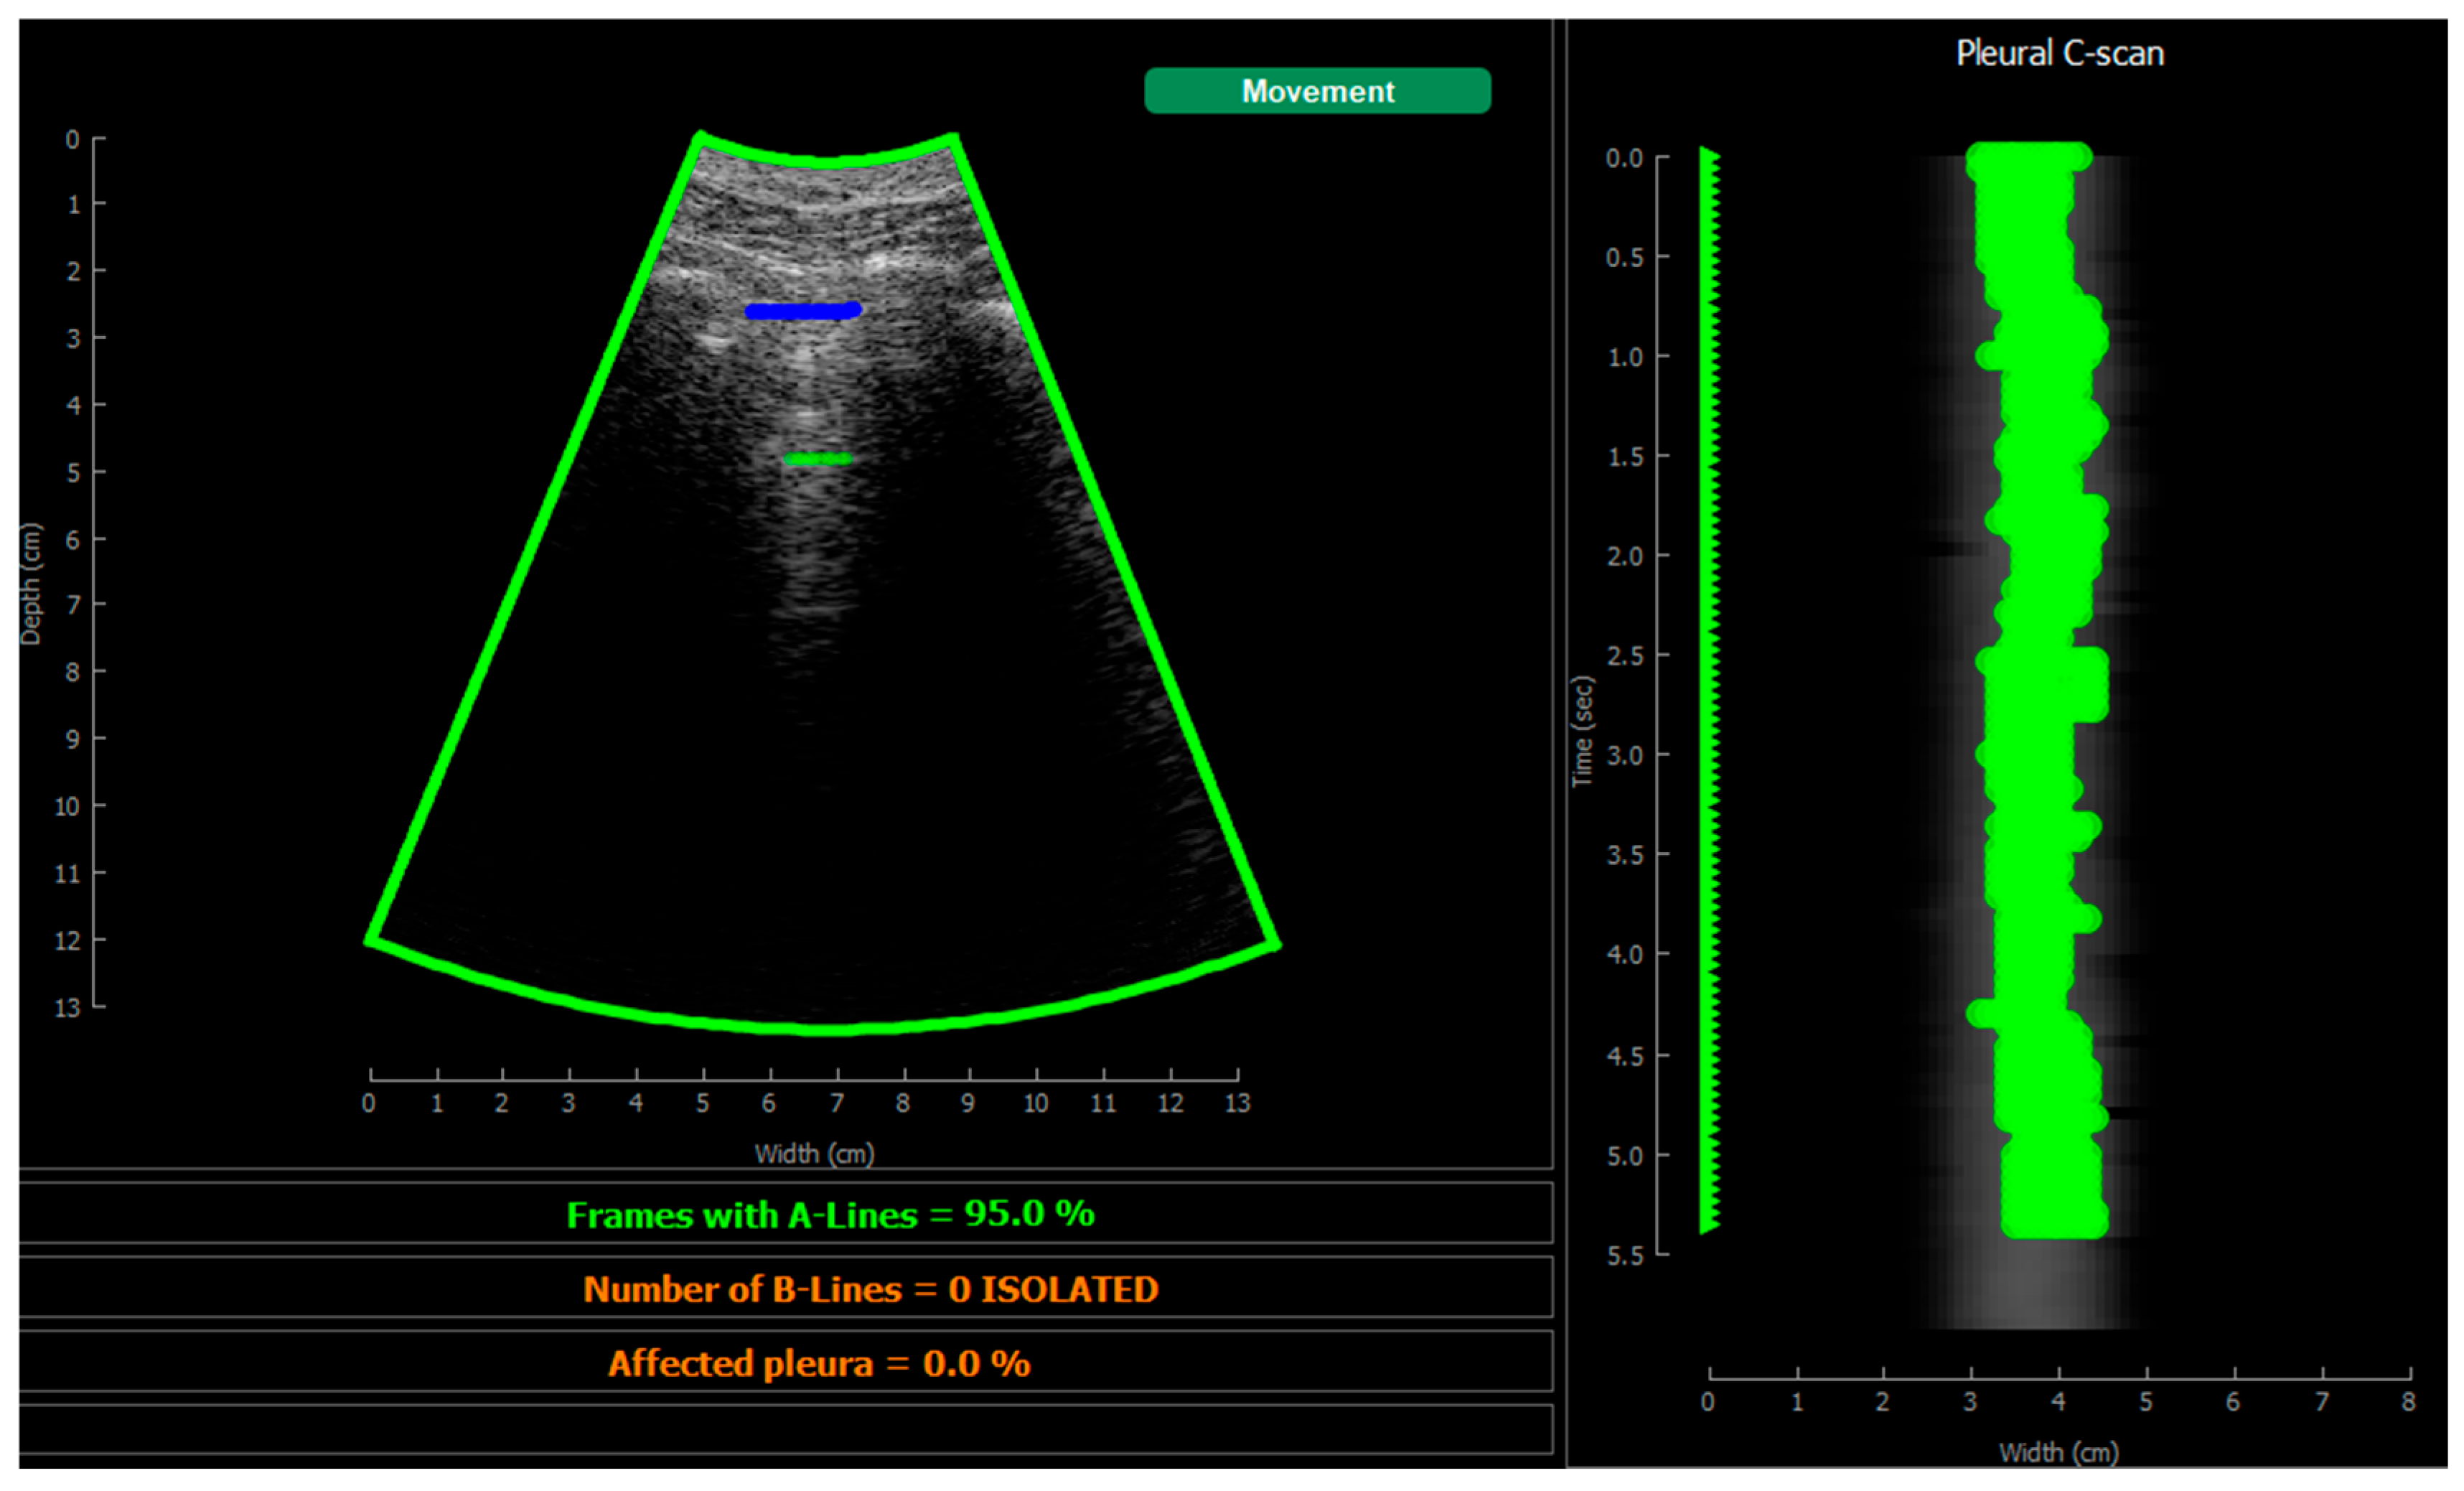

Figure 13.

Visualization screen.

This image also overlays, in real-time, the findings of the neural network. The pleura is marked with blue points, A-Lines with green points, B-Lines with orange points, and consolidations with red points. Furthermore, a series of statistics and messages are shown in the lower part of this image: the percentage of frames with A-Lines in the last 6 s; the number of isolated B-Lines, calculated as the sub-regions with an average 6 dB drop in the angular direction within the region where B-Lines were detected; the percentage of the affected pleura calculated as the number of scan lines affected by B-Lines over the total number of scan lines where the pleura was detected; and a label in red indicating that a consolidation when present.

On the right of the screen, an image we refer as pleura C-scan is shown. The C-Scan is a type of image widely used in Non-Destructive Testing (NDT) applications where B-scan images are acquired while the probe is moving and a visual representation of the whole component is needed [33]. For each image line within the B-Scan, the maximum amplitude is obtained within a gate at some depth, which assembles an ensemble image that can be interpreted like a top view of the component, with defects information at a certain depth. We adapted this concept using a gate at the depth of the pleura, obtained from the pleura mask given by the model, and substituting the mechanical movement of the probe in an NDT scan, by the time index in the acquired video. Therefore, each horizontal line in the pleura C-Scan correspond to a frame in the video, and it shows the brightness of the pleura line along the horizontal dimension of the image. At each of these lines, landmarks with the previously defined colours are also plotted. As the video progresses, the C-Scan image is constructed frame by frame from top to bottom and, at the end, all the relevant information of the video is condensed in only one image. The presence of A-Lines, B-Lines, and consolidations and their extension with regard to the pleura width can be appreciated, and also the pleura sliding effect as the indications move laterally during the scan. Furthermore, these images could be saved for each acquired region in the chest and shown in a single panel that depicts the global condition of the lung in a single view, without the need to review each of the acquired videos for the whole examination, which could help to reduce time during follow up of patients.

Figure 16 shows several examples of the screen of the implemented software in operation explained in Section 2.5.4.

Figure 16.

Application visualization sample: (a) B-lines (orange) and consolidation (red) detection; (b) normal lung with A-lines (green); (c) probe movement detected; (d) B line (orange) and A-line (green) deteccion on a Lung phantom. On the right of each image the C-scan image is shown.